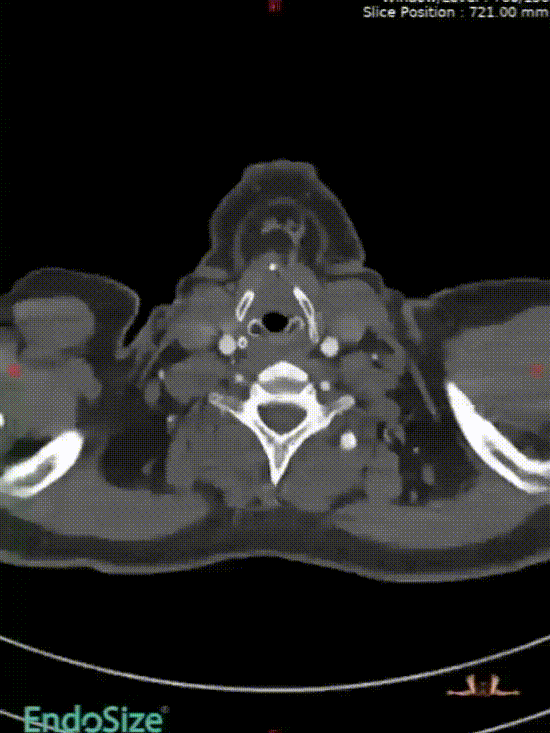

病史:54岁男性,发现胸腹主动脉夹层动脉瘤四天,2011年曾行A型夹层手术史,术后10年未复查。

手术方案:全麻下行胸腹主动脉夹层覆膜支架腔内隔绝,CA、SMA、双侧肾动脉体外开窗重建术。

I期腔内修复过程:

肾动脉至肠上区无破口,病情进展后又进行了二期干预

胸腹主动脉瘤四开窗内脏区重建+远端髂总大破口栓塞

术后效果良好,各分支通畅